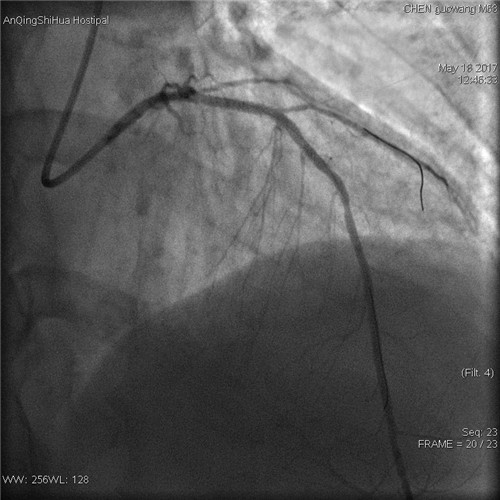

術(shù)后 前降支支架內(nèi)狹窄解除

術(shù)者先用普通預(yù)擴張球囊預(yù)處理病變,后以與支架匹配的切割球囊于病變處擴張,在對病變血管充分預(yù)處理后,再用藥物球囊持續(xù)擴張。復(fù)查造影顯示,殘余狹窄<20%,血流通暢,未見明顯的夾層、慢血流等并發(fā)癥,“介入不植入”藥物球囊治療大獲成功。